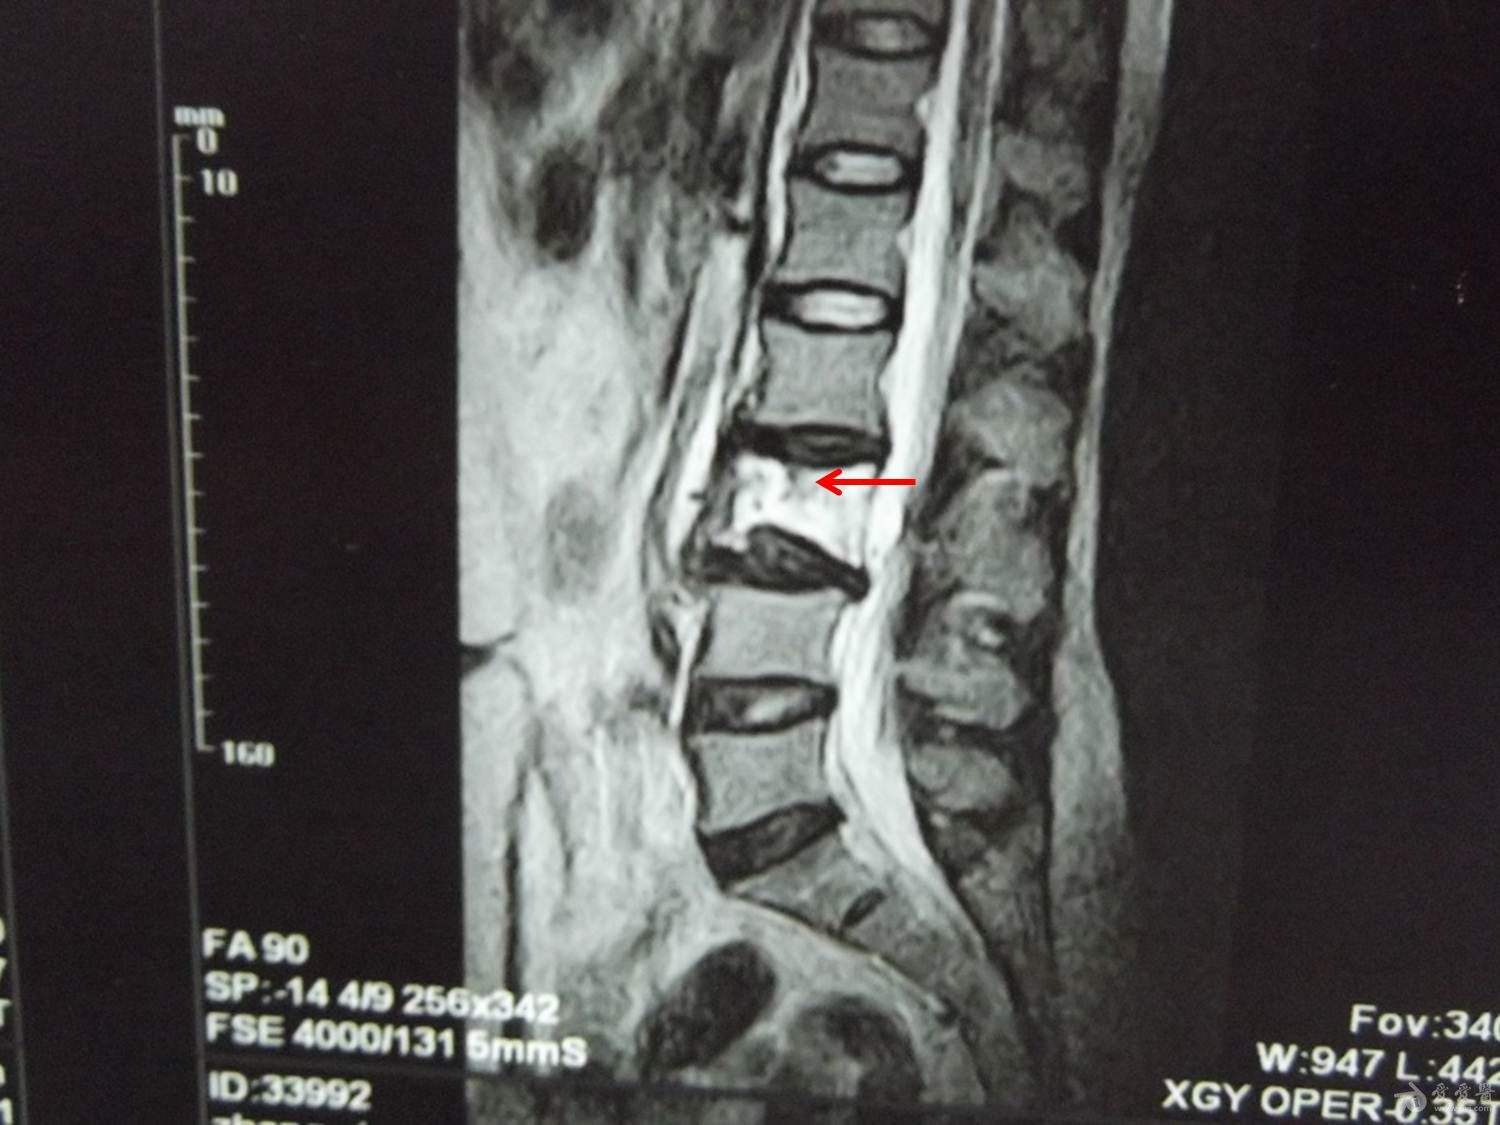

(5)椎体血管瘤:椎体血管瘤若侵及椎弓根、横突,或突破骨皮质,会有疼痛和相应神经症状。如果病变导致椎体压缩性骨折或椎弓根破坏可以先行手术减压,并在术后给予放射治疗。